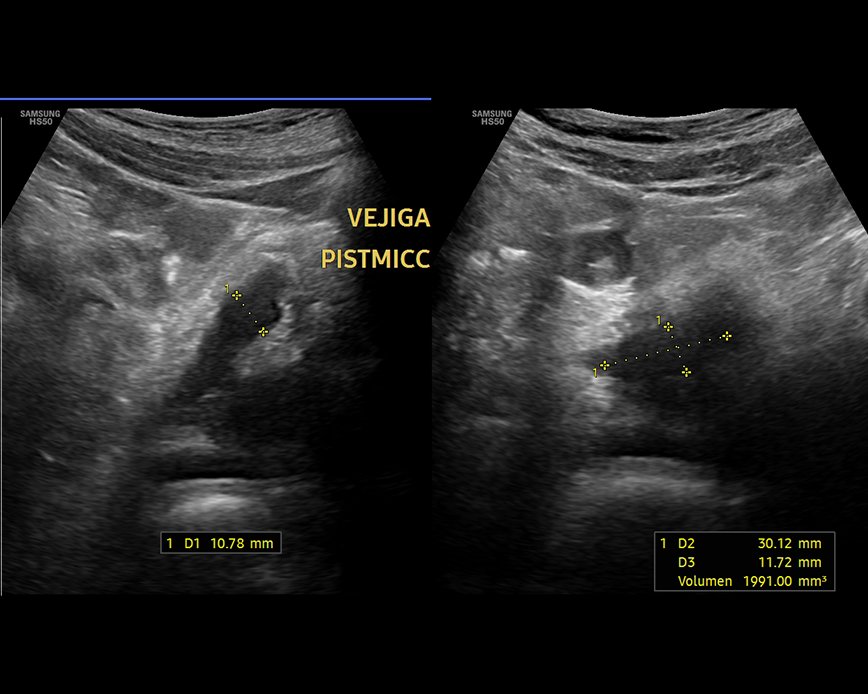

Ecografía Abdomen superior

- Estudio de la vesicular biliar y vías biliares